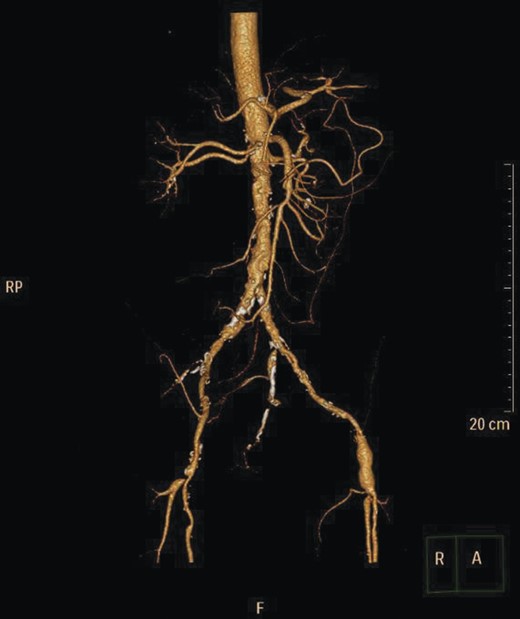

Given the high likelihood of significant vascular disease, a computed tomography (CT) angiogram was done (Fig. 1). Bilateral internal iliac artery stenosis was noted with complete occlusion of the inferior mesenteric artery and right internal iliac artery. A positron emission tomography (PET) scan showed only localized disease (Fig. 2). Magnetic resonance imaging (MRI) of his pelvis was significant for a large posterior abscess cavity with soft tissue at the margins with a cavity tracking superiorly along the posterior rectal plane (Fig. 3). The internal sphincter was noted to be necrotic on the last examination (Fig. 4) with a horseshoe cavity and a 10-cm tract running up the posterior aspect of the rectum. Multiple biopsies were taken from the anal margin, abscess cavity and peri-anal tissue, and the histology was consistent with diffuse large B-cell lymphoma. There were sheets of large atypical lymphocytes with extensive areas of necrosis. The tumour cells showed strong and diffuse immunohistochemical reactivity for CD20 (Fig. 5), indicating B-cell differentiation. The Ki67 proliferation index was very high (>90%) (Fig. 6) and there was positive in situ hybridisation (ISH) for Epstein-Barr virus (EBV) (Fig. 7). Fluorescence in situ hybridisation (FISH) was performed using a MYC dual colour break apart probe (8q24), and no rearrangement of the MYC gene region was detected. The combined morphological and FISH features were not considered to be those of Burkitt lymphoma.

CT angiogram showing IMA and right internal iliac artery completely occluded.